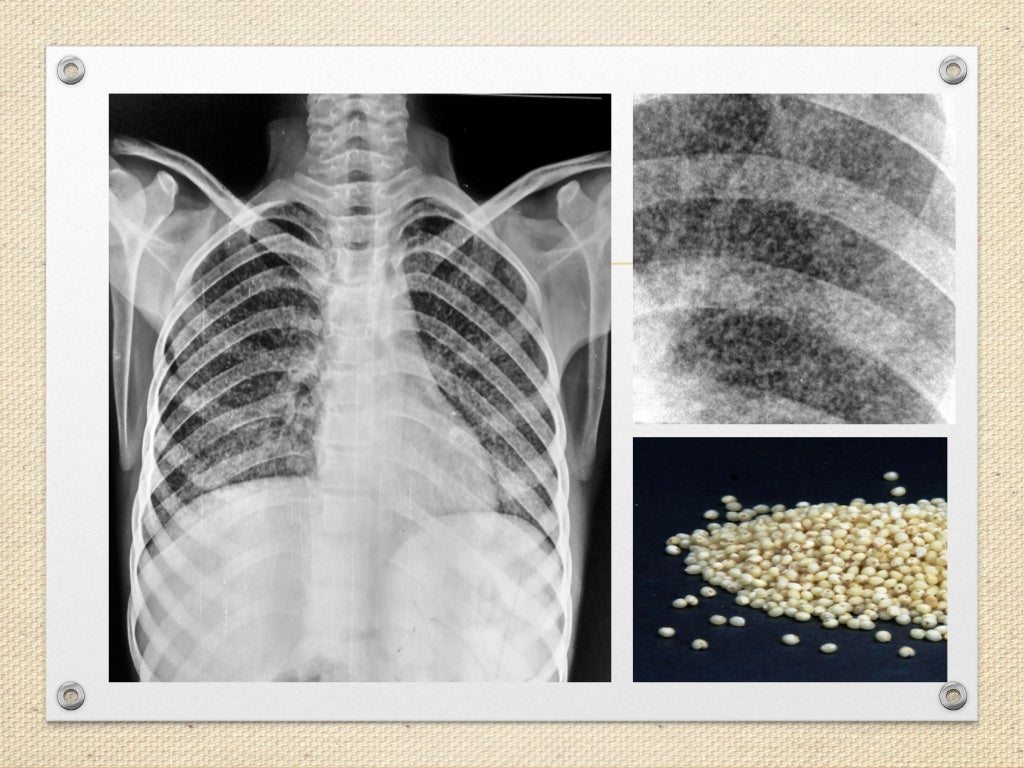

Millet seed appearance on CXR in a patient with Miliary MEDizzy Millet Seed X Ray Miliary tuberculosis is a rare form of tuberculosis that affects the lungs and other organs. Miliary tuberculosis is a severe form of tuberculosis (tb) caused by the dissemination of mycobacterium tuberculosis bacteria throughout. Learn about its pathology, radiographic features,. Widespread hematogenous dissemination of mycobacterium tuberculosis. Miliary tuberculosis is a severe form of tb caused by hematogenous dissemination of mycobacterium tuberculosis.. Millet Seed X Ray.

This anteroposterior (AP) chest xray revealed the presence of numerous Millet Seed X Ray Widespread hematogenous dissemination of mycobacterium tuberculosis. Miliary tuberculosis is a severe form of tuberculosis (tb) caused by the dissemination of mycobacterium tuberculosis bacteria throughout. Miliary tuberculosis is a rare form of tuberculosis that affects the lungs and other organs. So named because the nodules are. Learn how to identify and differentiate the four patterns of interstitial lung disease (ild) on. Millet Seed X Ray.

(A) Millet seeds appearance of the lungs due to miliary tuberculous Millet Seed X Ray Learn about its pathology, radiographic features,. So named because the nodules are. Miliary tuberculosis is a severe form of tuberculosis (tb) caused by the dissemination of mycobacterium tuberculosis bacteria throughout. It is useful to divide these. Widespread hematogenous dissemination of mycobacterium tuberculosis. Learn how to identify and differentiate the four patterns of interstitial lung disease (ild) on chest radiographs and. Millet Seed X Ray.